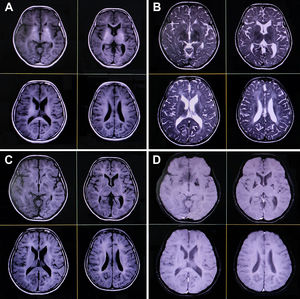

Magnetic resonance imaging of the brain reveals symmetrical hypomyelination of the hemispheric periventricular white matter with early ventricular dilatation, calcification of bilateral basal ganglia and thalamus, and dysgenesis of the corpus callosum (axial T1-weighted [A], T2-weighted [B], fluid-attenuated inversion recovery [C], and gradient echo sequences [D]).

A neurologic examination revealed she had mental retardation with an intelligence quotient of 80. Ophthalmological and fundus examinations were normal. There was no cranial nerve, motor, sensory, autonomic, or cerebellar deficit except for symmetric hyporeflexia-to-areflexia (more than lower limbs). Complete blood cell count and metabolic-endocrinological panel were within acceptable normal range. Pure-tone audiometry and brainstem-evoked response audiometry studies were normal. A brain computed tomography scan revealed early cortical atrophy with extensive calcifications in the cerebellum, basal ganglia, and periventricular regions. Brain magnetic resonance imaging showed symmetrical (slightly parieto-occipital predominant) hypomyelination of the hemispheric periventricular white matter with early ventricular dilatation, basal ganglia, thalamus, and dentate calcification, dysgenesis of the corpus callosum, and mild cerebral and cerebellar atrophy with shrunken folia and enlarged cisterna magna (Fig. 2). Nerve conduction studies showed axonal sensorimotor polyneuropathy with a low amplitude of sensory nerves (right median 6.16μV; left median 6.97μV; right ulnar 4.59μV; left ulnar 5.31μV; right sural 1.89μV; left sural 1.48μV) and motor nerves (right median 2.4mV distal/2mV proximal; left median 1.7mV distal/1.2mV proximal; right ulnar 2.3mV distal/2mV proximal; left ulnar 2mV distal/1.6mV proximal; right tibial 1.3mV distal/1mV proximal; right common peroneal 1.2mV distal/1.0mV proximal; and left common peroneal without response). The amplitude of the left tibial nerve was normal (6.1mV). The latency and conduction velocity of all the nerves and needle electromyography findings were otherwise normal. The results of electrocardiography, 2D and M-mode echocardiography, and abdominal ultrasonography were also normal.